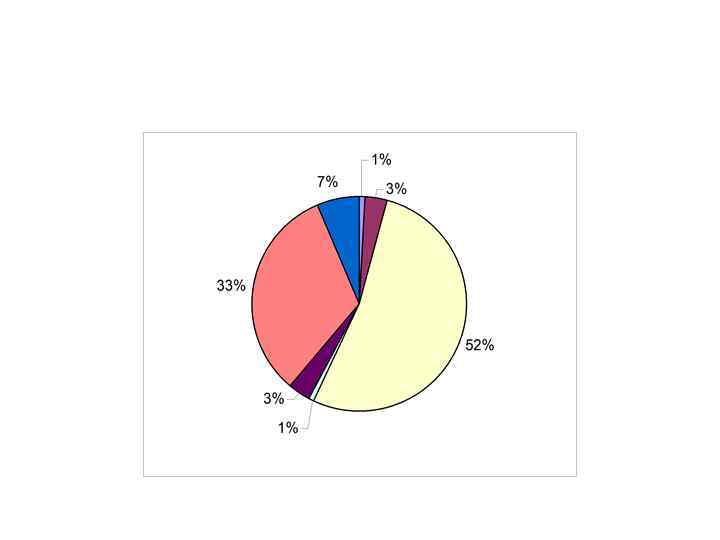

• Клинико-диагностическое значение лабораторных показателей в гематологии • РАМН ГНЦ, академик А. И. Воробьев, 2001 • • МАЗОК КРОВИ Нормальная лейкоцитограмма взрослых: Нейтрофилы палочкоядерные 1 -5% Нейтрофилы сегментоядерные 40 -50 % Лимфоциты 20 -45% Моноциты 3 -8% Эозинофилы 1 -5% Базофилы 0 -1%

• Клинико-диагностическое значение лабораторных показателей в гематологии • РАМН ГНЦ, академик А. И. Воробьев, 2001 • • МАЗОК КРОВИ Нормальная лейкоцитограмма взрослых: Нейтрофилы палочкоядерные 1 -5% Нейтрофилы сегментоядерные 40 -50 % Лимфоциты 20 -45% Моноциты 3 -8% Эозинофилы 1 -5% Базофилы 0 -1%

• В окрашенных мазках крови подсчитывают лейкоцитарную формулу + процентное соотношение разных видов лейкоцитов. Исследование лейкоцитограммы состоит в дифференциации в мазке 200 -500 расположенных подряд лейкоцитов.

• В окрашенных мазках крови подсчитывают лейкоцитарную формулу + процентное соотношение разных видов лейкоцитов. Исследование лейкоцитограммы состоит в дифференциации в мазке 200 -500 расположенных подряд лейкоцитов.